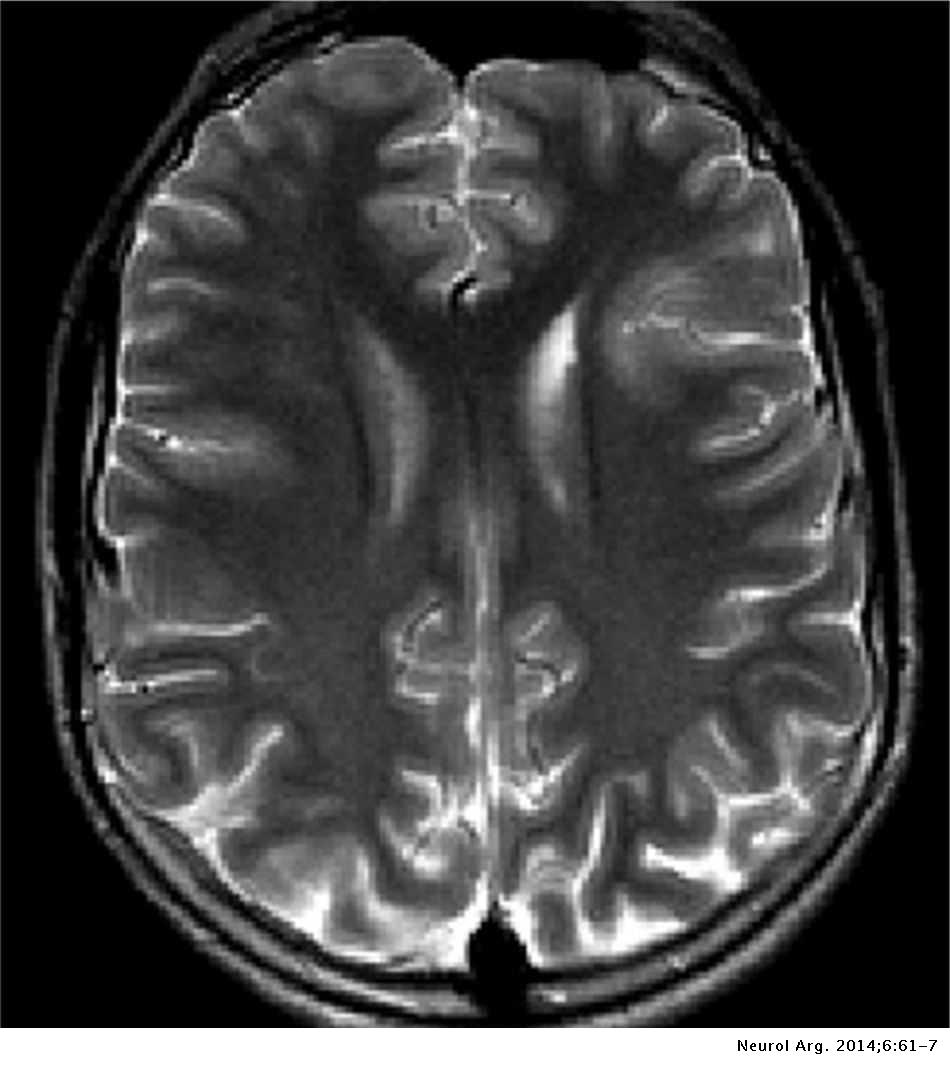

Lista muestra hermosas imágenes de resonancia magnética cerebral normal y anormal dinosenglish.edu.vn para que puedas explorar más en detalle.

resonancia magnética cerebral normal y anormal Pin en NEUROCIENCIAS resonancia magnética de cerebro Resonancia magnética (RM) de cerebro, corte axial ponderado en T2: la … VIDEO Nueva mancha en la Resonancia

Engineer Team : RESONANCIA MAGNETICA Magnetic Resonance Imaging – Clinical Images Hallazgos por resonancia magnética cerebral de nuestro paciente. M, 21 … Imágenes por resonancia magnética anormales como predictoras de mal … Imágenes por resonancia magnética anormales como predictoras de mal … Lesiones en resonancia magnética (RM) del encéfalo y la médula espinal … Pin en Resonancia Magnética del Encéfalo A) Resonancia magnética cerebral (RMC) mostrando infartos en … Caso 1: Edema cerebral visualizado mediante RM. (A) Secuencia T1 plano … Rascacielos dormir pasta tac y resonancia diferencias retrasar … Pin on Apuntes de Enfermería y T.C.A.E Resonancia magnética cerebral secuencia T2, que muestra lesión … Meningitis aguda en la enfermedad de Behçet | Reumatología Clínica Resonancia magnética coronal normal del cerebro Fotografía de stock – Alamy Imágenes de resonancia magnética, la imagen de la cabeza en diferentes … Resonancia magnética cerebral A) protocolo T1 sagital (Caso 1). Se … Resonancia magnética cerebral. Secuencia T1 corte sagital. Atrofia … Resonancia magnética de cerebro, cortes axiales, secuencias T2. Señal … Resonancia magnética de cráneo. A y B) Cortes axiales FLAIR … Resonancia magnética (RM) de cerebro, corte axial ponderado en T2: la … RM cerebral: Interpretación paso a paso | Kenhub Resonancia magnética de cerebro, cortes axiales, secuencias T2. Señal … De Resonancia Magnética De Cerebro Foto de archivo – Imagen de arteria … Top 107+ Imagenes de resonancia cerebral normal – Destinomexico.mx -Imagen por resonancia magnética del cerebro. a) Cortes sagital y axial … resonanCia magnétiCa Cerebral donde se observa hiperintensidad a nivel … MRI (Imagen de resonancia magnética) – Tomografía computarizada de la … Meningioma – NCI Imágenes por resonancia magnética coloreadas del cerebro sano del … Resonancia magnética cerebral en secuencia FLAIR, que muestra lesiones … Contraste resonancia magnetica cerebral – senturinthegreen Relación de los espacios de Virchow-Robin con la enfermedad de … Gliomatosis cerebral – Instituto Nacional del Cáncer Pin en Neurology. Recomendaciones para la utilización e interpretación de los estudios de … Fotografía De La Proyección De Imagen De Resonancia Magnética Del … atmósfera Dirigir Cumplir anatomia resonancia magnetica Desarrollar … Pin en #MEDICINA,#SALUD Resonancia magnética de la nasofaringe De Resonancia Magnética De Cerebro Foto de archivo – Imagen de polilla … Atrofia cortical global de predominio parietal en la Resonancia … Resonancia magnética cerebral | Download Scientific Diagram Neuroblog: Resonancia magnética cerebral en la trombosis crónica de … De Resonancia Magnética De Cerebro Imagen de archivo – Imagen de … ¿Cuáles son los riesgos de la resonancia magnética? – Integra Salud … Resonancia magnética cerebral al decimocuarto día de ingreso: área … Resonancia magnética. Corte axial mostrando área infartada en el … Resonancia magnética cerebral del paciente AV evidenciando lesiones en … -Ressonância magnética de encéfalo mostrando múltiplas imagens … Resonancia magnética cerebral secuencia FLAIR (Fluid Attenuated … Resonancia magnética cerebral con protocolo de epilepsia, en sección … Resonancia magnética cerebral en corte sagital. Se observa una evidente … Resonancia magnética craneal en la que se evidencian lesiones … Logran visualizar el cerebro a detalle más completo tras una resonancia … Así decide el cerebro la severidad de un castigo De Resonancia Magnética De Cerebro, Imagen de archivo – Imagen de … A) Resonancia magnética cerebral; Secuencia Tof: oclusión de arteria … Un estudio asocia la ansiedad con la aparición rápida del Alzheimer IMÁGENES DE 18 F-PR04.MZ PET FUSIONADA CON RESONANCIA MAGNÉTICA … Imágenes por resonancia magnética anormales como predictoras de mal … Tumores de la región pineal – Instituto Nacional del Cáncer Epilepsia: una historia de voces y fantasmas | Neurología Contribución de las imágenes de resonancia magnética por tensor de … Resonancia magnética secuencia T2 plano coronal de quiste epidermoide … Resonancia Magnética Cerebral del paciente: a. Aumento de… | Download … Resonancia magnética cerebral 2022 Síndrome de hemiconvulsión-hemiplejía-epilepsia. Seguimiento de un caso … Enfoque Radiologico: La resonancia magnética permite detectar lesiones … Resonancia magnética craneal T1 con contraste que muestra angiomatosis … guidewiz – Blog Resonancia magnética cerebral, secuencia SWI. Ribete hipointenso en la … resonAnCiA mAgnétiCA de ColumnA Con gAdolinio. Corte sAgitAl en t1 de … SEMANA 12: FUNDAMENTOS DE RESONANCIA MAGNÉTICA NUCLEAR. INDICACIONES Y … DIAGNÓSTICO DE ESCLEROSIS MÚLTIP Magnetic resonance imaging of the brain – Alchetron, the free social … Resonancia magnética de órbitas | Instituto Radiológico Dr. E Castillo Alteración de la marcha en un paciente post-trasplante hepático Resonancia magnética cerebral de un paciente sano (Ay B) y paciente que … Utilidad de la resonancia magnética craneal para el diagnóstico de la … Resonancia Magnética Del Cerebro El Tumor Cerebral Foto de stock y más … De Resonancia Magnética De Cerebro Imagen de archivo – Imagen de … ABDALLA RADIOLOGIA: NEURINOMA ACUSTICO Atrofia cortical global de predominio parietal en la Resonancia … Resonancia Magnética : Producción de la imagen MRI Brain Scan — Stock Photo © Bunyos30 #18724051 Mri (imagen de resonancia magnética) Monitor con imagen de captura de … Tomografía computarizada vs resonancia magnética: diferencia y … Tumores Cerebrales – Unidad de Neurocirugía RGS Resonancia magnética de la columna, sección sagital. Observe los discos … La resonancia magnética, una técnica imprescindible en el diagnóstico … Perfusión Cerebral por Resonancia Magnética | ¿Qué es? ¿Necesita Contraste? Resonancia Magnética Cerebro A: resonancia magnética, T2 coronal preoperatoria; se observa lesión en … Resonancia magnética cerebral — Foto de stock © Bunyos30 #27340623 La resonancia magnética se perfila como detector de mentiras | Futuro … Resonancia magnética cerebral en T1 con gadolinio, cortes axial (a … MRI brain : show brain tumor at right parietal lobe of cerebrum — Stock … NEUROIMÁGENES EN ENFERMEDAD DE PARKINSON: ROL DE LA RESONANCIA …